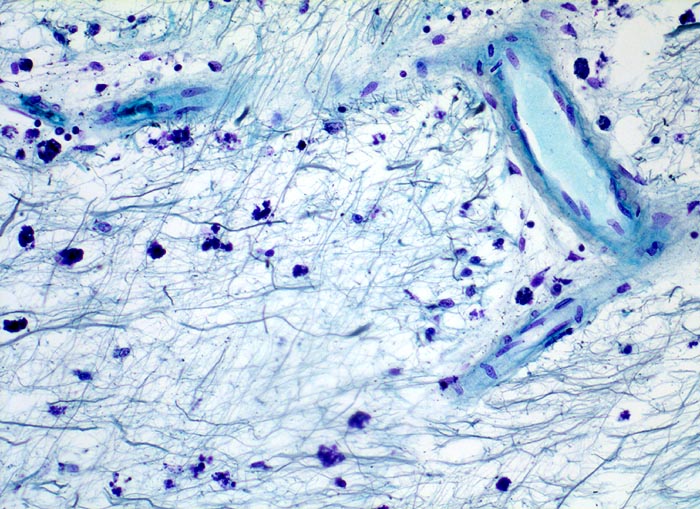

Ausschnitt aus einem älteren Entmarkungsherd. Zwischen den übgriggebliebenen Axonen lassen sich mit Myelinbruchstücken beladene Makrophagen nachweisen. Vereinzelte mononukleäre Entzündungszellen sind vorwiegend perivaskulär lokalisiert. Oligodendrogliazellen sind nicht sicher erkennbar.